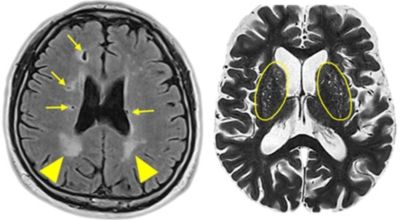

후두엽 혈관이 막히게 되면 뇌경색 초기증상으로 시야가 결손되거나 복시 현상이 생겨나게 되어요. 단순 시력 저하가 아닌 글씨나 물체가 겹쳐 보이고 뚜렷하게 보이지 않는 증상이 나타나게됩니다. 동일한 시력 저하는 시력이 서서히 나빠지는 양상을 보이지만 뇌경색의 경우에는 갑작스럽게 시력이 저하되거나 한쪽 눈이 아예 보이지 않을 수도 있어요. 바로 막힌 혈관에 피가 쏠려 혈관이 부풀어 올라 다른 혈관이나 신경들을 누르면서 한쪽 눈이 실명되는 시력 장애가 나타나는 경우입니다.

5. 뇌경색 초기증상 - 복시